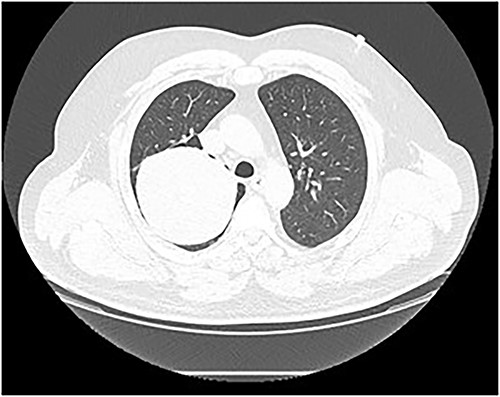

Chest computed tomography (CT) revealed a well-defined solid nodule (Fig. 2). Bronchoscopy and transbronchial biopsy were performed. On pathology, no specific findings were found. The bronchoscopy was repeated, and a transbronchial cryobiopsy was performed. On pathology, an abundantly vascularized SFT was verified.

Chest CT scan. A well-defined solid nodule of 10 cm in diameter in the right upper lobe.